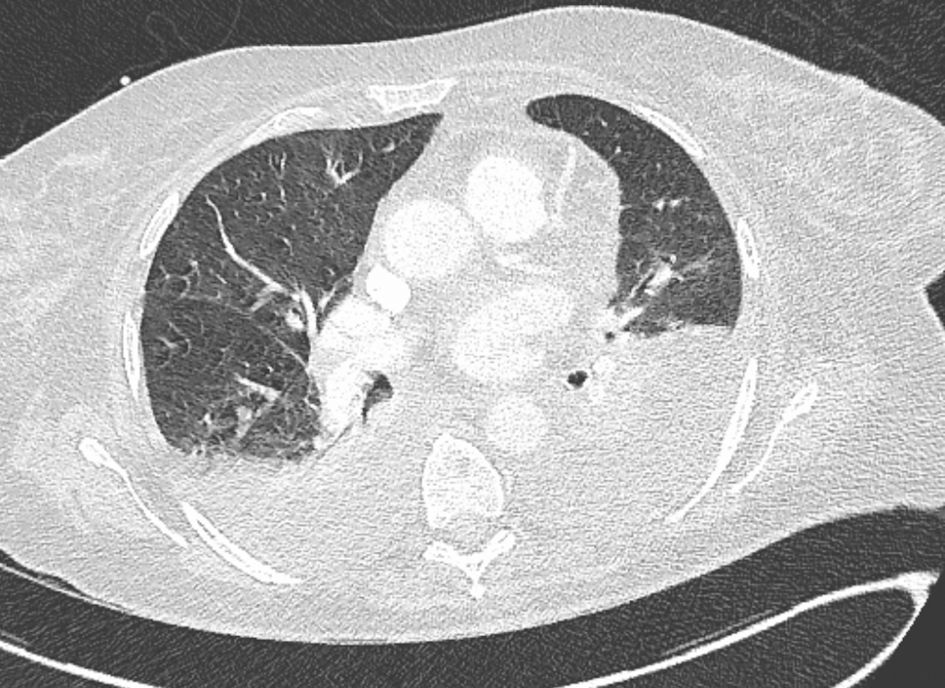

Two days later, the patient developed acute respiratory distress requiring oxygen. Arterial blood gas analysis revealed respiratory alkalosis, and CT angiography confirmed bilateral pleural effusions associated with bilateral atelectasis (Fig. 3). We added levofloxacin to the antibiotic regimen to treat infections caused by intracellular microorganisms and Legionella.

![]() Click for large image | Figure 3. Chest CT revealed bilateral pleural effusions associated with right lower lobe atelectasis. CT: computed tomography. |